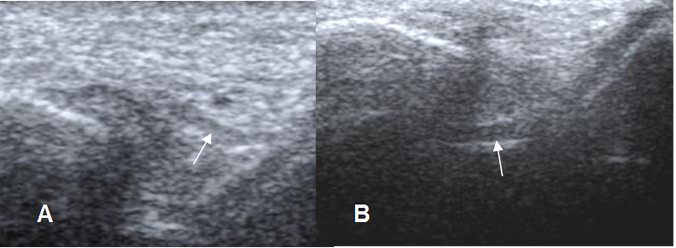

Fig 9. Ligamentos peroneoastragalinos normales en ecografía.

Ligamento peroneoastragalino anterior en A y peroneoastragalino posterior en B.